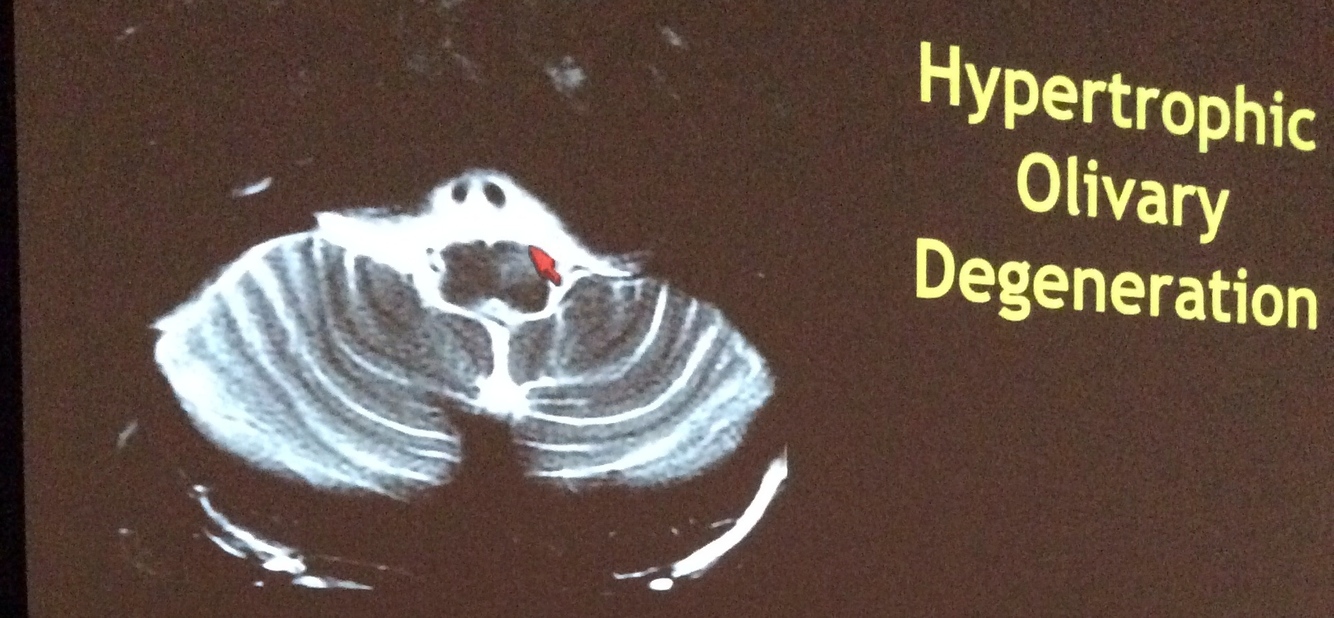

Hypertrophic Olivary Degeneration

• pathway disrupted - Guillian-Mollaret triangle

• most common symptom - palatal myoclonus